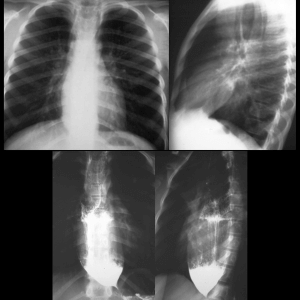

Congenital diaphragmatic hernia (CDH)

Diaphragmatic hernia